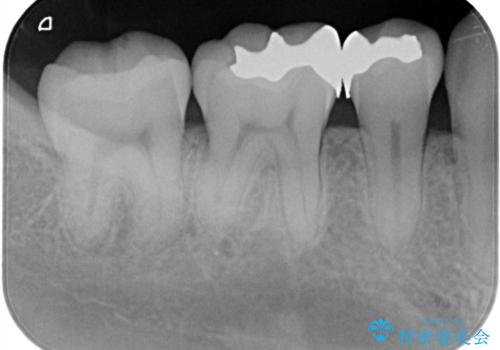

- 「銀歯を白しくしたい」を主訴に来院された患者さんです。

銀歯を外し、虫歯を除去した後にハイブリッドインレーで治療を行いました。